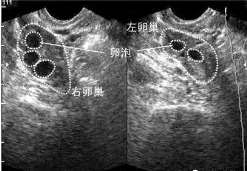

504 好孕百科患有卵巢囊肿会影响怀孕吗? 一般来说,卵巢囊肿是良性肿瘤。只要囊肿小,不影响月经,就不会影响怀孕。提示腹痛可能 […]